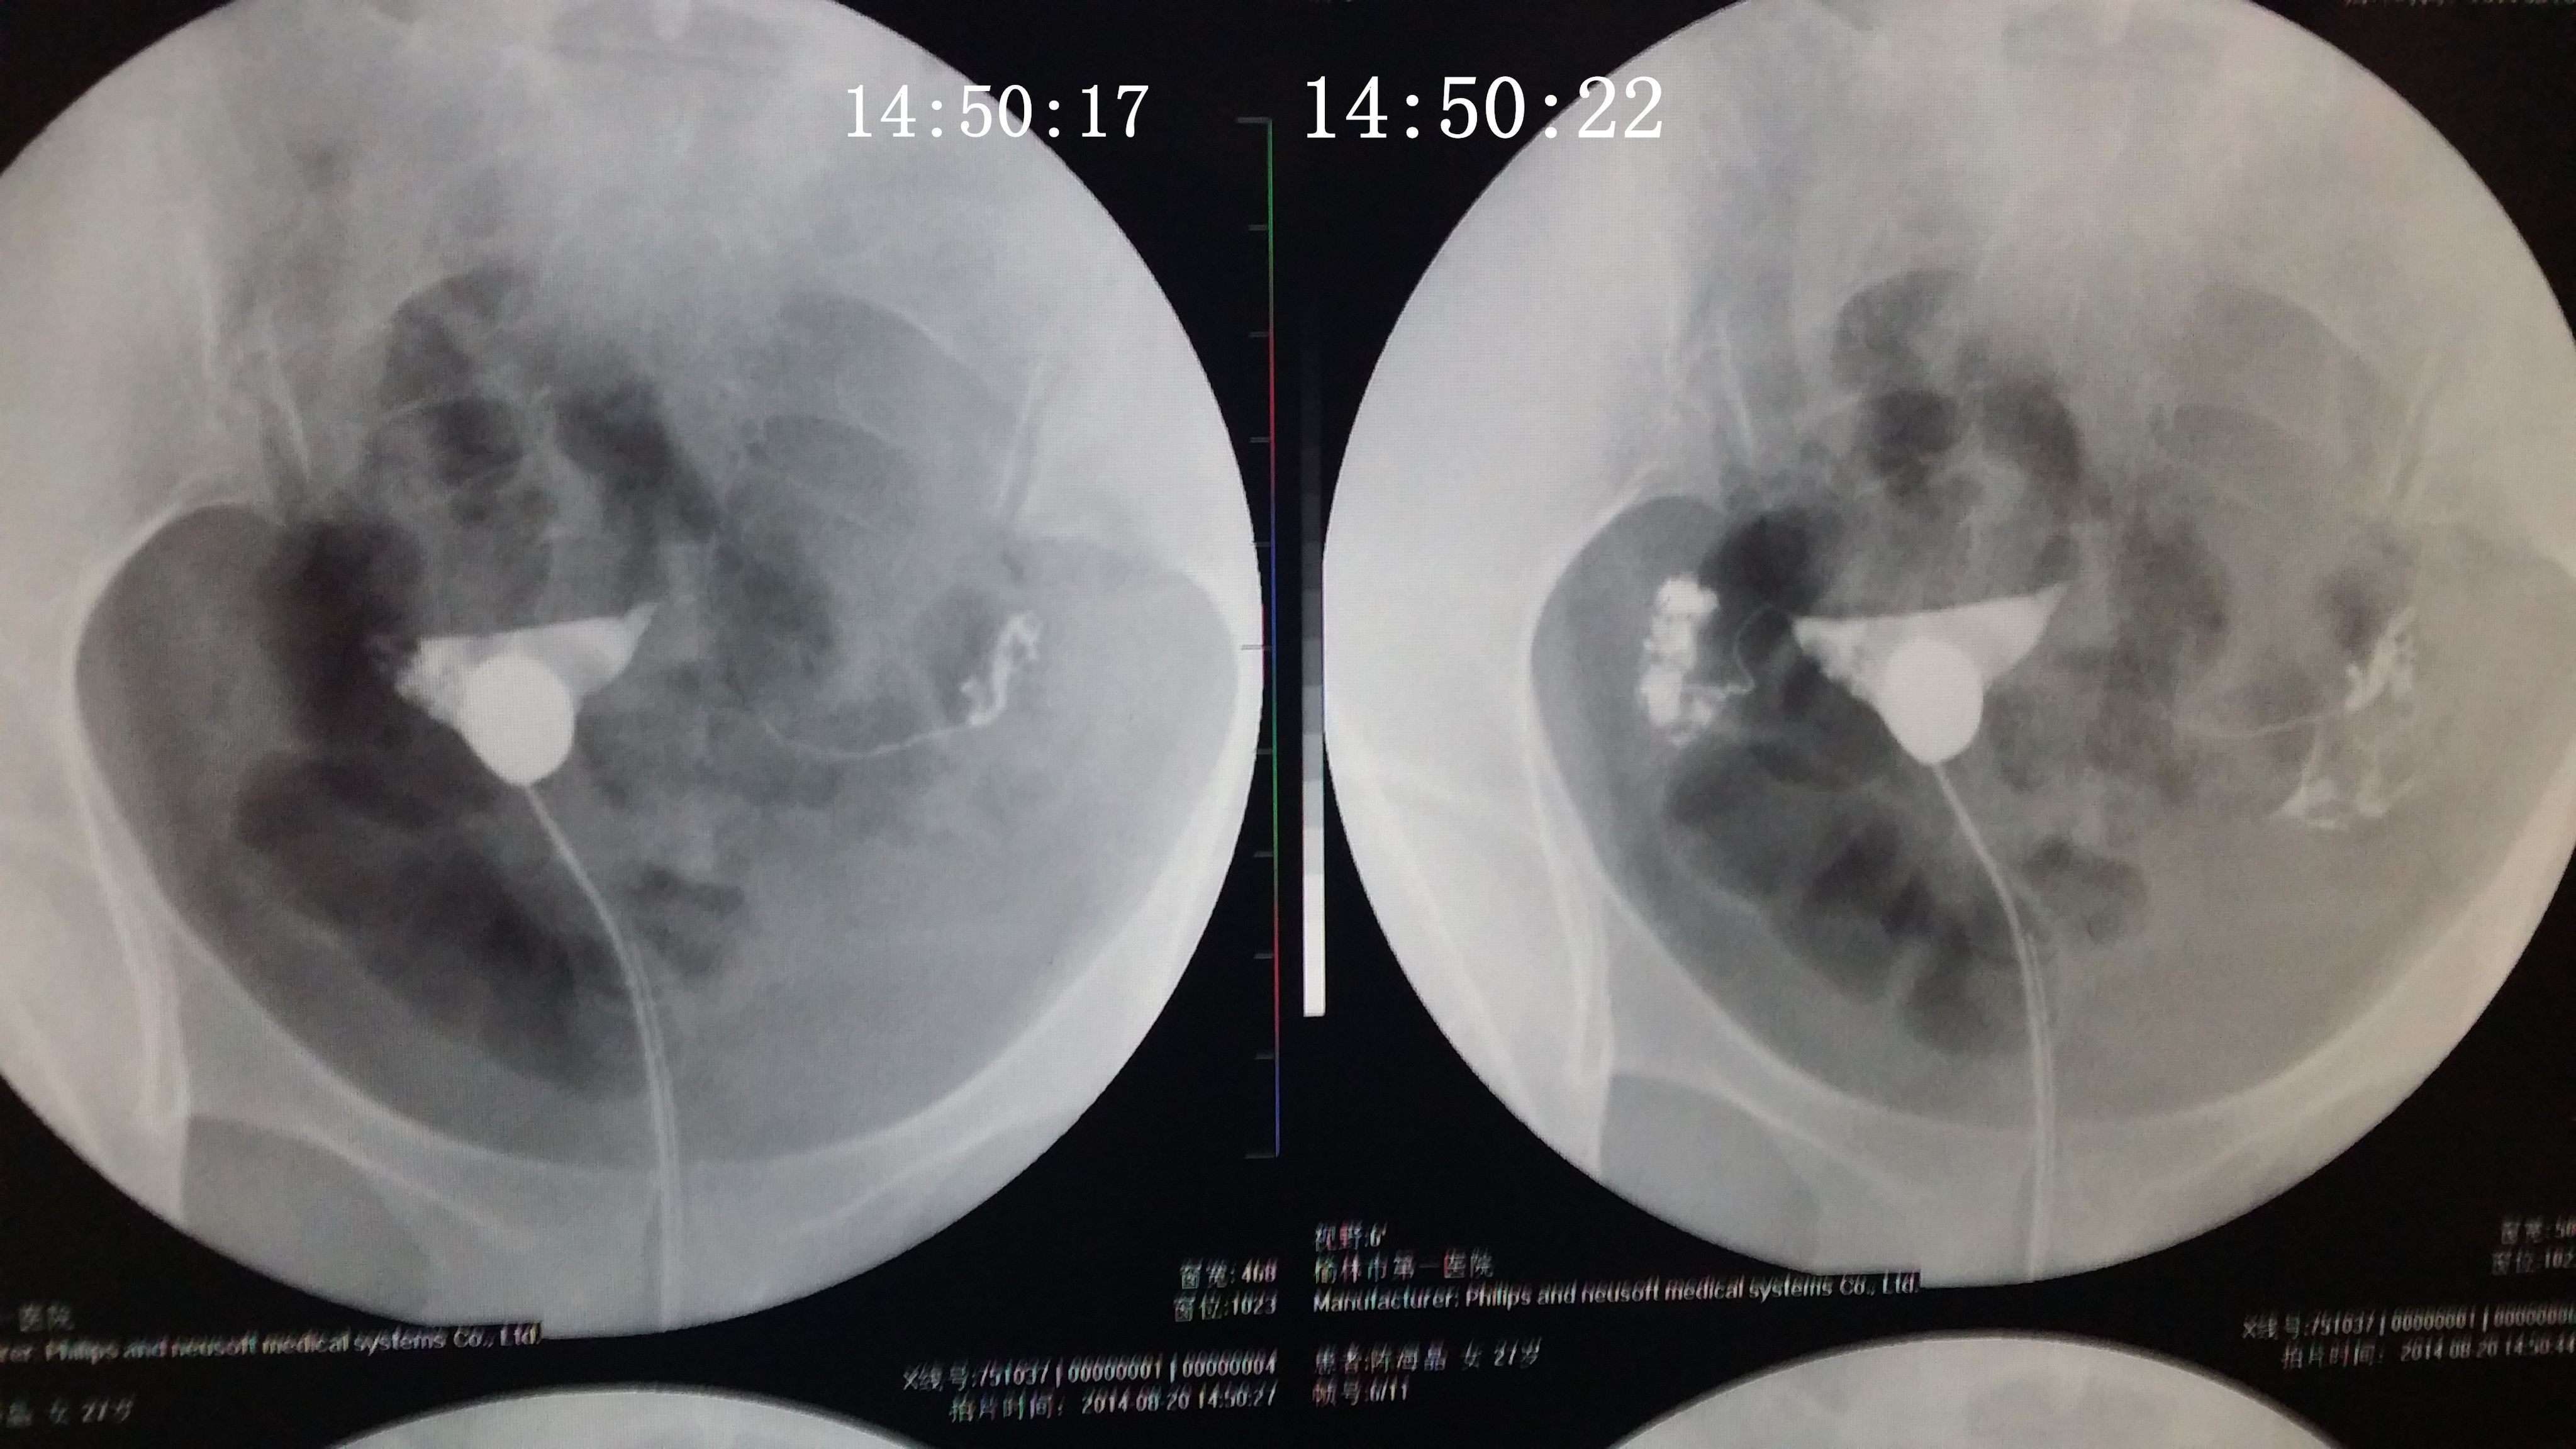

请专家帮我分析下我的造影片 医生诊断说是没问题,只是右侧输卵管伞部有点弯曲不直,说左侧通着可以自 然受孕,不知道会不会有错,之前在其他医院没做造影直接做的通液,说是阻力很大,堵的厉害,后过几个月在另一家医院做的这个造影片。(另之前有过盆腔积液,但已经治疗好了} 造影都好几天了右侧一直觉得酸痛的,是不是又发炎了啊,吃药可以吗? 点击展开 匿名用户 2014-09-04 20:08 为您推荐: 其他回答 你好,现在这个时候你不要太担心的竟然是已经检查过了之后的话那就不要剪的啦,因为这个时候已经通开了, 可靠的悠闲80 2014-09-05 12:50 相关问题 输卵管通而不畅,迂曲右侧上举,请问济南哪个大医院治疗这个专业啊~请有经验的人告诉下~急急急另附造影片 输卵管伞端不通怎么办 如果排了,B超能检测出来吗?B超单上会显示什么?12月22号做的造影,结果是右侧输卵管伞端通而不

然受孕,不知道会不会有错,之前在其他医院没做造影直接做的通液,说是阻力很大,堵的厉害,后过几个月在另一家医院做的这个造影片。(另之前有过盆腔积液,但已经治疗好了} 造影都好几天了右侧一直觉得酸痛的,是不是又发炎了啊,吃药可以吗?